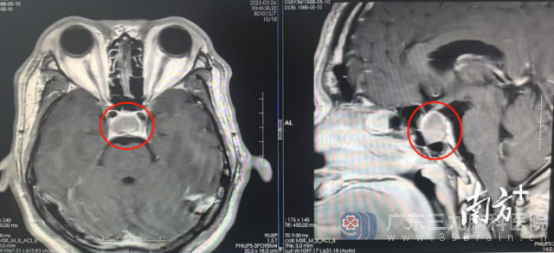

完善相关检查后,鲁明团队从患者鼻孔“打洞”,顺利切除一个大小为19mm×15mm×19mm的生长激素型垂体瘤。

影像检查提示:鞍区占位